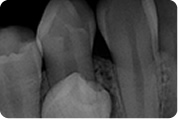

RTG / RVG

Digitalna tehnika snimanja zuba rtg /rvg aparatom omogućava nam trenutni prikaz stanja zuba i čeljusne kosti. Ordinacija je opremljena potpuno novim uređajem za rtg snimanje zuba sa minimalnim dozama ionizirajućeg zračenja. Kodak 2200 i Kodak 5100 i digitalnim senzorom za intraoralne snimke zuba.

Povećana pouzdanost dijagnostike

Kodakov visoko frekventni generator omogućuje postizanje snimaka vrlo visoke kvalitete, dok istovremeno maksimalno smanjuje izloženost radijaciji. Sa žarišnom točkom od 0.7 mm i preciznim usmjerenim zračenjem, Kodak 2200 pruža visoko kvalitetnu i preciznu snimku sa raznolikim stupnjem sivog spektra.

Maksimalna kvaliteta slike – Minimalna izloženost zračenju

Ovisno o anatomskom području slikanja, tjelesnoj težini pacijenta i vrsti filma ili senzora koji se koristi, Kodak 2200 sistem automatski podešava vrstu i vrijeme ekspozicije zračenja. Ta preciznost omogućuje maksimalnu redukciju izloženosti radijaciji.